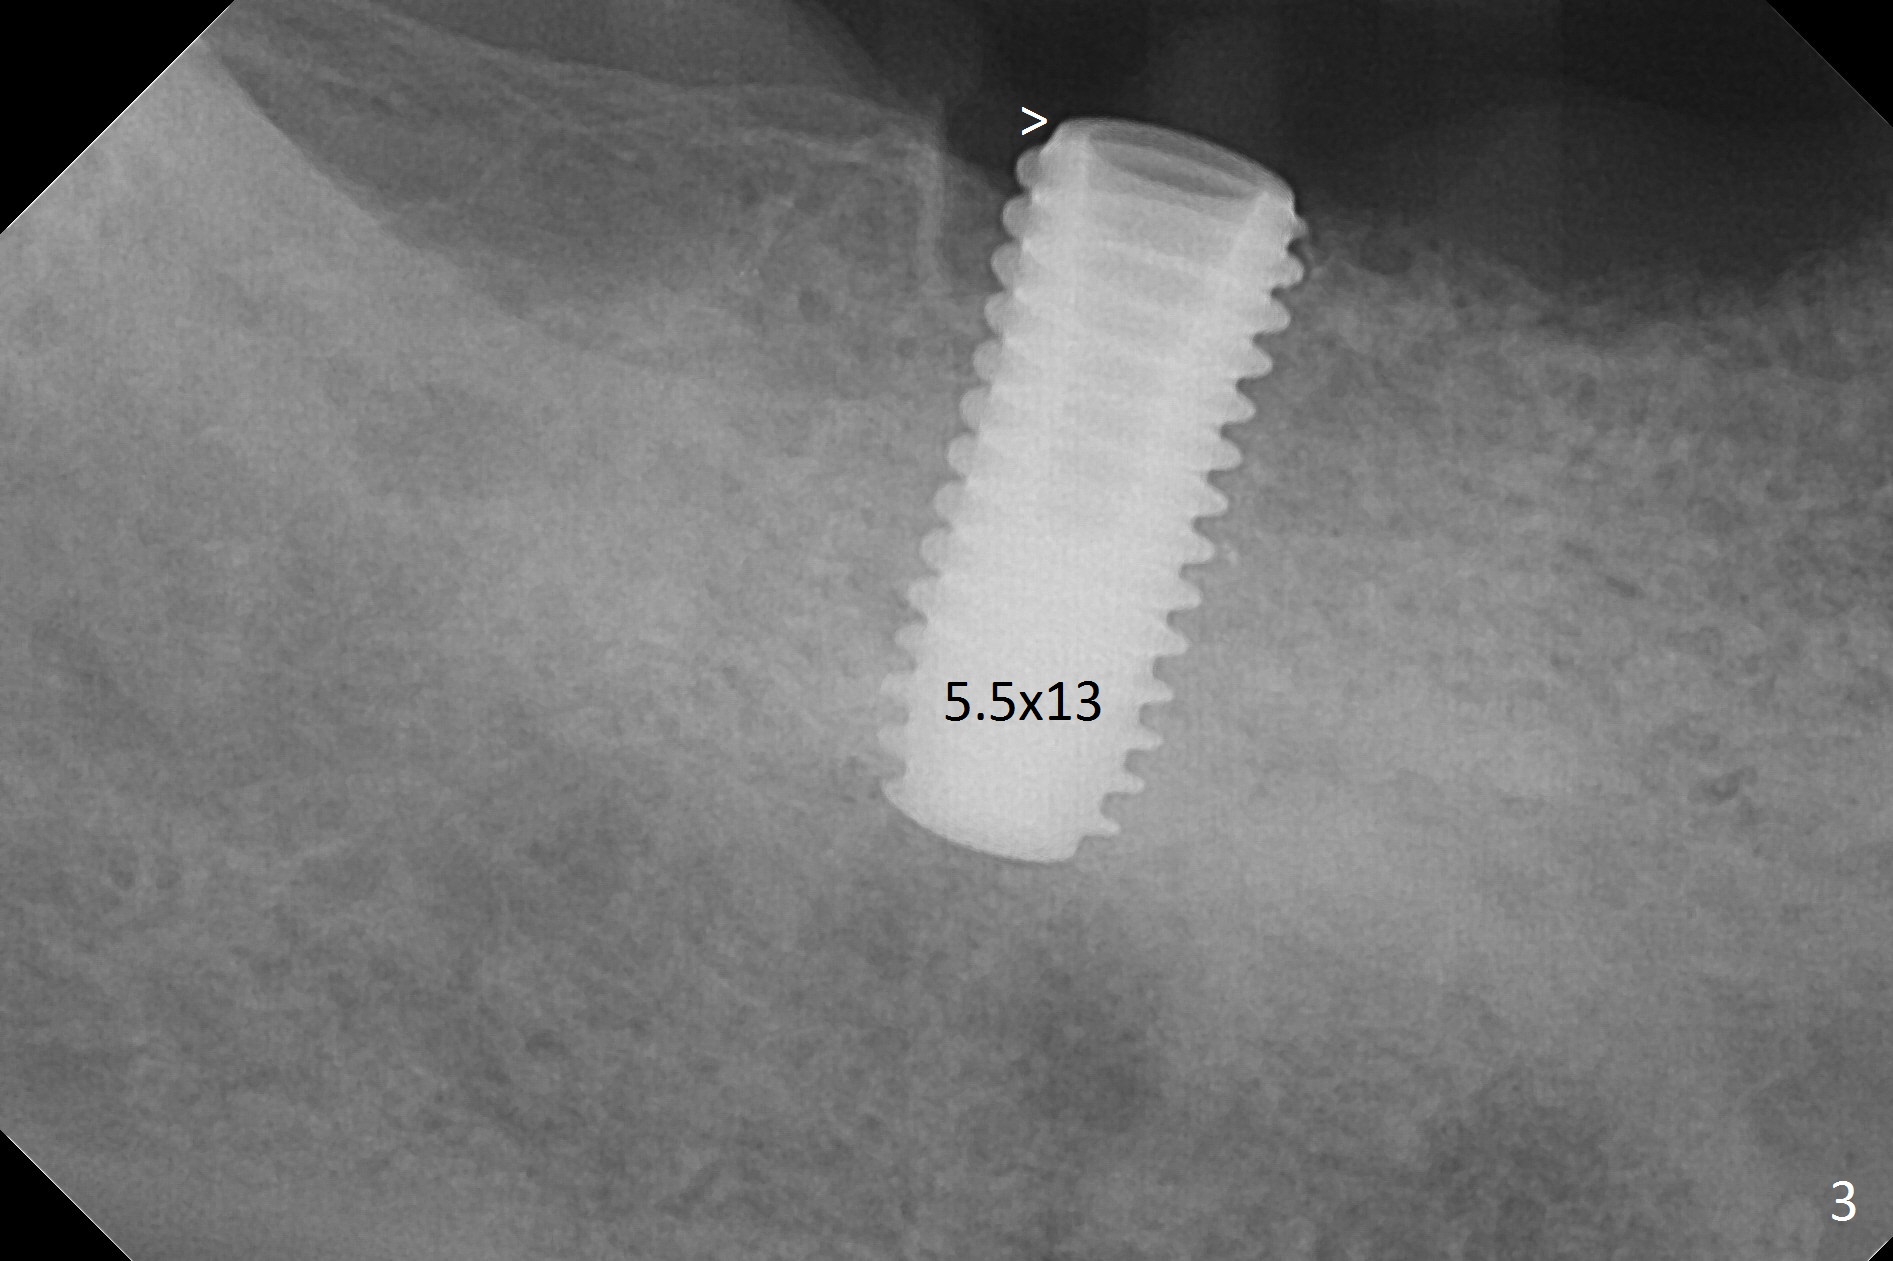

There are 2 challenges associated with #31 implant placement: indistinct Inferior Alveolar Canal (Fig.1-4) and difficulty in fabrication of a provisional (Fig.5).  After placing a 5.5x13 mm implant (Fig.3 supracrestal (<)), it is removed for apical resection for ~ 2 mm; when it is reseated, it is subcrestal (Fig.5 <).  A simplified temporary provisional (Fig.5 P) is fabricated around a 6.5x4(4) mm abutment (A) without adapting the lower RPD.  The patient is advised not to wear the latter.  When the socket heals, there will be 2 options: no provisional or a new one.  The latter should have good retention to the abutment and no contact with the lower RPD in and out.